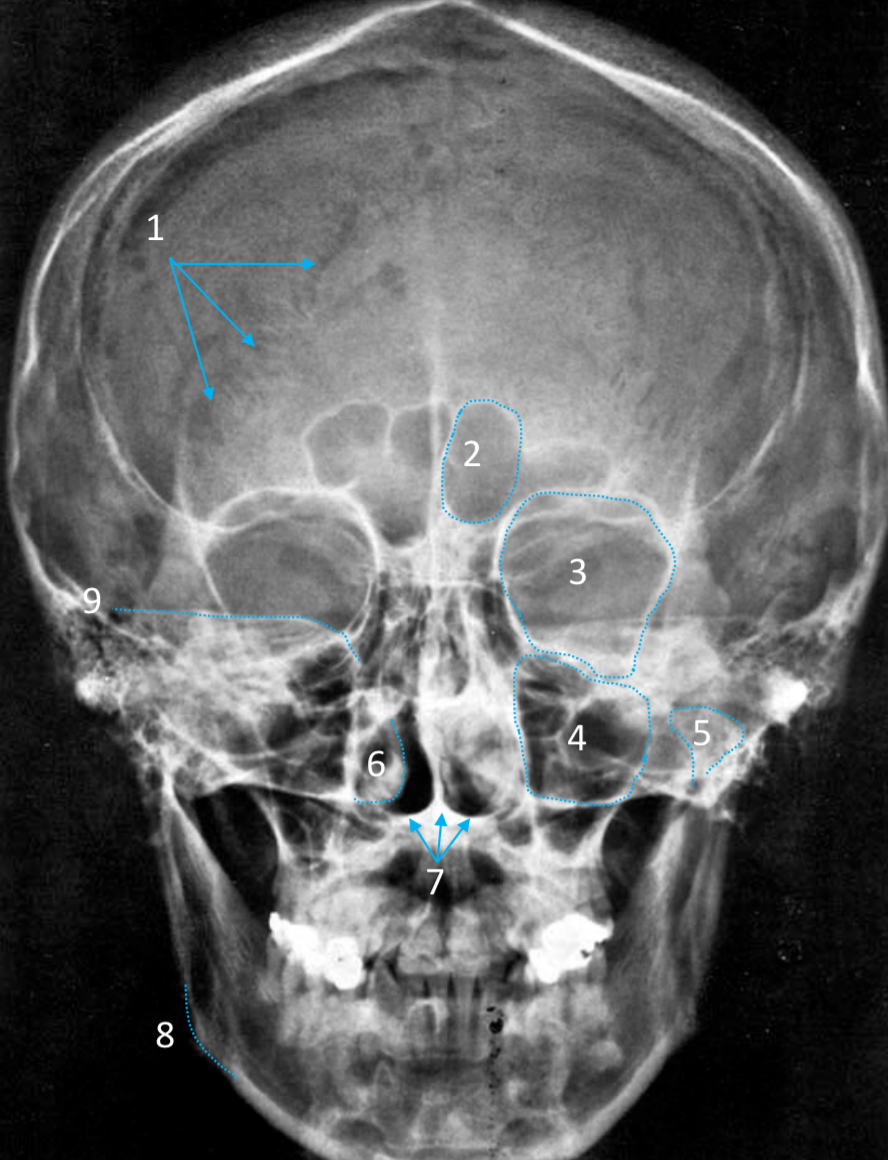

Frontal sinus

ID structure

Pituitary fossa

ID structure

Frontal sinus

ID structure

Orbital margin

Orbit

Maxillary sinus

ID structure

Mandibular condyle

ID structure

Inferior nasal concha

ID structure

Hard palate

ID strucutre

Gonial angle

ID strucutre

Petrous ridge

ID structure

Groove of middle meningeal a.

ID structure

Roof of orbit

ID structure

Frontal sinus

ID structure

Pituitary fossa

ID structure

Petrous ridge

ID structure

Sphenoid sinus

ID structure

Hard palate

ID structure

Mastoid air cells

ID structure

Zygomatic arch

ID structure

Mandibular condyle

ID structure

External auditory meatus

ID structure

Mastoid air cells

ID structure

Foramen magnum

ID structure

Foramen ovale

ID structure

Foramen spinosum

ID structure